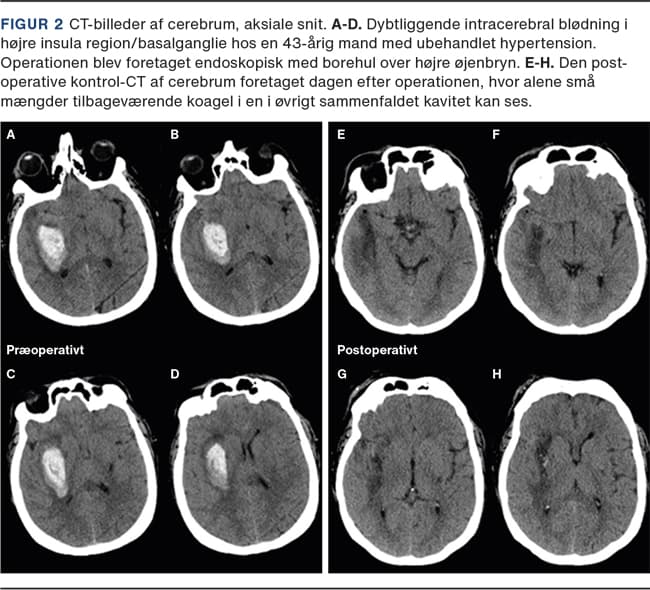

I Figur 2 og Figur 3 vises to sygehistorier med dybtliggende ICH i basalganglier, hvor begge er fjernet med endoskopisk operationsteknik. Begge patienter har haft et kort (24 timers) forløb i et neurointensivt afsnit, hvorefter neurorehabilitering kunne påbegyndes.